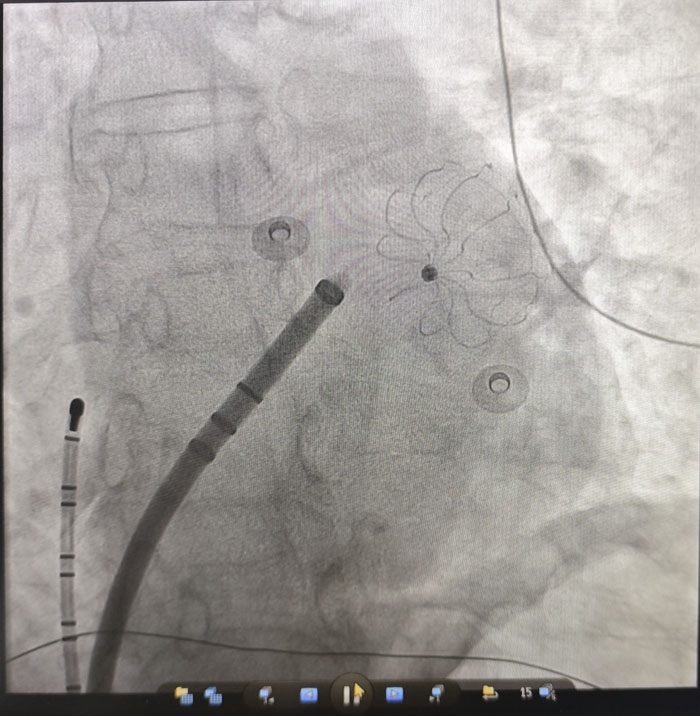

在房颤治疗方面,团队成功开展“房颤射频消融+左心耳封堵”一站式手术。患者为67岁女性,受房颤困扰多年,心悸、胸闷反复发作,生活质量严重下降,同时面临高卒中风险。传统房颤治疗通常需分别处理心律转复与抗凝问题,过程繁琐,对患者依从性要求较高。经全面评估与多学科讨论,团队决定采用微创介入技术,在一次操作中同步解决两大问题:射频消融精准定位并消除心脏内引发房颤的异常电信号,帮助恢复窦性心律,从根源上改善心慌、胸闷等症状;同时针对房颤患者约90%的血栓来源于左心耳的特点,植入封堵器封闭这一“血栓工厂”,从源头上预防脑卒中等血栓栓塞事件。

手术过程顺利,术后复查显示,患者心律已恢复为正常的窦性心律,左心耳封堵器位置良好、无残余分流。次日,患者即可下床活动,恢复迅速。该一站式诊疗方案,为高卒中风险、高出血风险,或无法耐受长期服药的房颤患者,提供了一次手术、双重获益的优质解决方案。